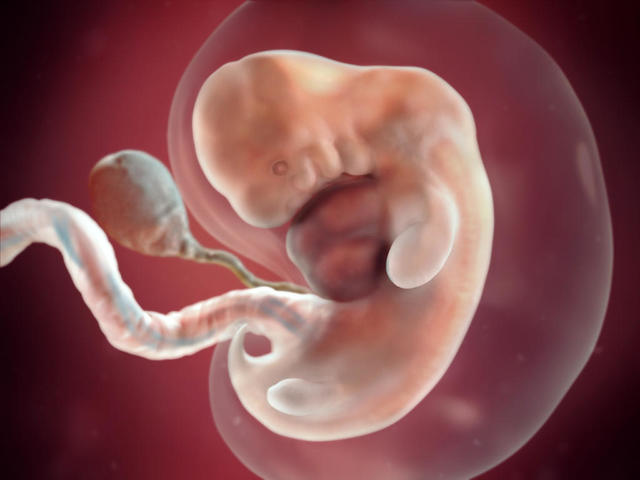

A partir de esta semana se comienzan a dar las primeras formas debido a que ya no hay más división celular; todas las celulas forman una sola y dan como resultado un cuerpo en proceso de desarrollo

El blastocisto antes mencionado ahora recibe el nombre de "embrión".

Se forman:

*Orejas,ojos y corazón en fase primaria.

*Cavidades para: huesos, músculos, riñones, pulmones, intestinos y sistema digestivo

*Tubo neural.